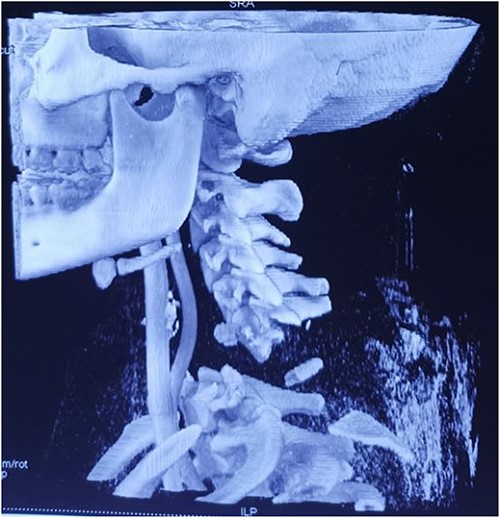

Computed tomography revealed complete traumatic dislocation of C6/C7 with consequent transection of the spinal cord (Figs 1 and 2).

Computed tomography finding (3D reconstruction): C6/C7 dislocation.